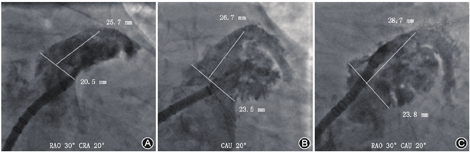

利用猪尾导管在左心耳内造影,确认猪尾导管进入左心耳,一般通过"三体位"造影图像来确认左心耳的形态:(1)RAO+头位(cranial,CRA),即右肩位,如RAO 30°~45°+CRA 20°(图2A);(2)左前斜位(left anterior oblique,LAO)+足位(caudal,CAU),如LAO 0°~15°+CAU 20°(图2B);(3)RAO+CAU,即肝位,如RAO 30°~45°+ CAU 20°(图2C)。不同患者造影角度可能会有所不同,为获得清晰的左心耳图像,可对造影角度进行调整。一般将"RAO+CAU"称为工作体位,在此体位下大多数患者左心耳能够充分展开,也可通过MSCT提前确定工作体位,在工作体位进行封堵器的展开,完成LAAO。

将猪尾导管置于左心耳的远端,尾端连接20 ml注射器;外鞘头端置于左心耳口部,尾端连接造影装置(如冠状动脉造影三联三通连接管、环柄注射器)。造影前确定X线透视工作模式以及视野大小(冠状动脉模式、帧率15幅/s为宜)。在鞘管以及猪尾导管中预充造影剂后再同时造影,可获得更清晰的左心耳影像。造影后,测量各个体位下的左心耳口部直径和可用深度,选择合适型号的封堵器,不同类型封堵器选择方式详见后述。